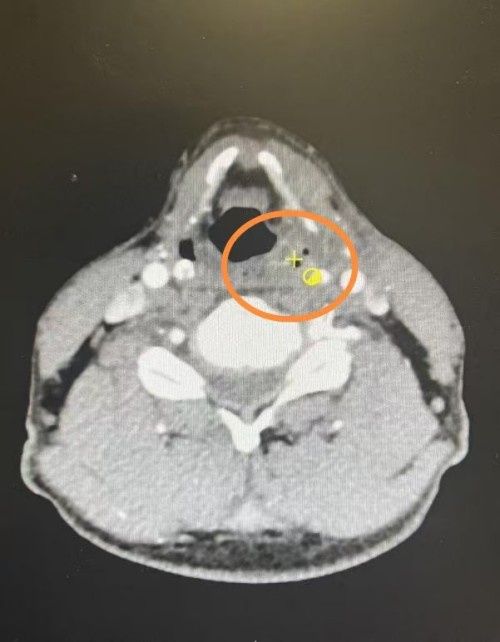

经过一次动脉灌注化疗后,复查显示患者梨状窝肿瘤明显缩小,双侧声带活动恢复正常,成功实现肿瘤降期。

治疗后